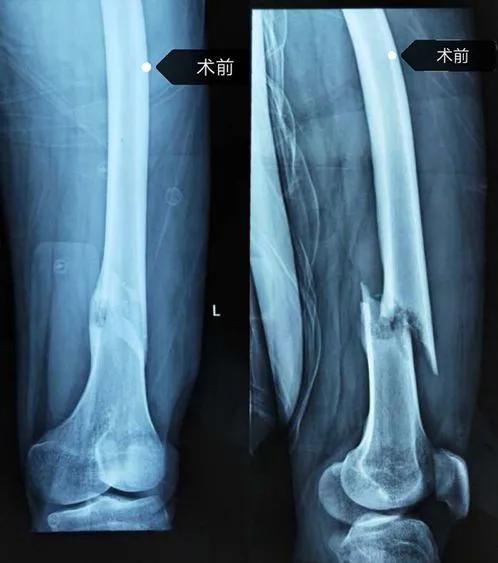

4月3日,34岁的张先生在行走过程中突然摔倒,左侧大腿疼痛难忍来到巴彦淖尔市医院创伤骨科就诊。然而入院后的影像检查让医生们觉得张先生的骨折并没有那么简单,在他骨折断端周围有一个病灶。经过胸片、肺部穿刺活检等相关检查后,确诊为股骨上甲状腺乳头状癌转移导致的病理性骨折。

左股骨瘤段骨切除骨水泥占位器植入骨折外固定及术后图片

手术由创伤骨科主任王金山主刀,据王金山介绍,张先生的手术分两次进行。第一次术中把肿瘤切除后旷置,依据CT扫描结果定制3D打印假体,在四周以后进行假体置入术。手术最大难度是肿瘤段骨完整切除,关键技术是诱导膜技术和私人订制3D打印假体。3D打印假体放入后,诱导膜促进骨质再生及修复,手术才能成功。做好充足的手术预案后,在麻醉科的协助下,创伤骨科团队成功将肿瘤切除,并将3D打印个性化定制的钛合金假体完美置入。此例手术由创伤骨科自主完成,该术的成功开展,标志着创伤骨科在应用3D打印技术实施骨肿瘤的个性化治疗中取得了新突破。